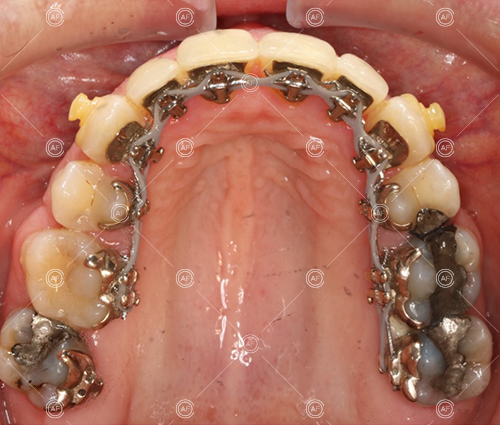

about this case…MH presented with class 1 incisors on the class 1 skeletal base with a slightly increased vertical proportion. She had severe crowding in the upper arch and moderate crowding in the lower. Due to the crowding in the lower arch, the lower centre line was off to the left by 2mm.

Buccal segments were essentially class 1 on the right hand side and a full unit class 2 on the left. This is due to buccal exclusion of the upper left 3 and mesial drift of the upper buccal segment.

- Extraction of upper right 5, upper left 4, lower left 5, lower right 5

- Fixed appliances in the upper and lower arches